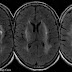

Diagnostic methods for hypertensive encephalopathy include physical examination, blood pressure measurement, blood sampling, ECG, EEG, chest X-ray, urinalysis, arterial blood gas analysis, and imaging of the head (CAT scan and/or MRI). Since decreasing the blood pressure is essential, anti-hypertensive medication is administered without awaiting the results of the laboratory tests. Electroencephalographic examination detects the absence of alpha waves, signifying impaired consciousness. In people with visual disturbances, slow waves are detected in the occipital areas.